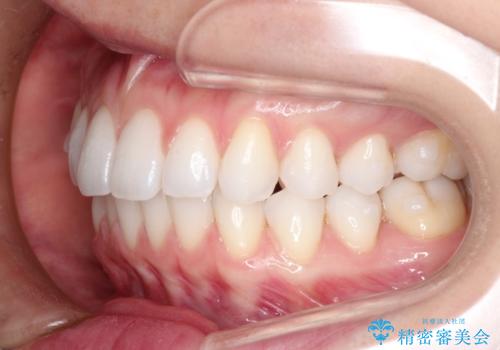

インビザライン中のホワイトニングについて

基本的に矯正中であってもホワイトニング自体は施術可能です。

マウスピース矯正用のマウスピースは、ご自宅で行うホームホワイトニング用のトレーとしてご利用いただくことができます。

※インビザライン治療の場合ホワイトニングを行う前歯にアタッチメントと呼ばれるポッチを歯の表面に付けることがあるため、アタッチメントがついた状態でホワイトニングを行うことはオススメしておりません。

右上の犬歯の歯茎は矯正前から退縮を起こしていましたが、矯正後もその退縮に関しては変化がありませんでした。今回は患者様が歯肉退縮に関しては治療をご希望ではありませんでしたが、当院ではこのように歯茎が下がり露出した根面を、歯茎を移植することでカバーし見た目を改善する手術を行っています。